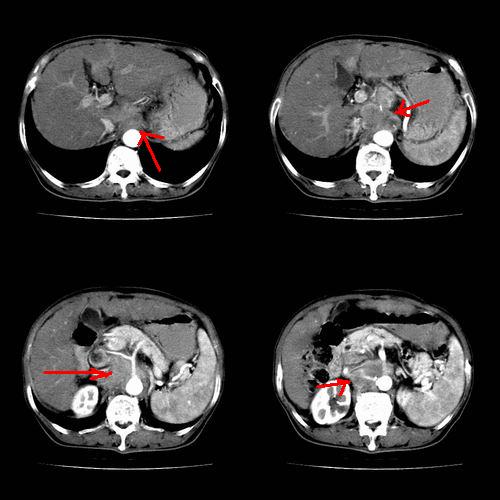

患者 女性 58岁,家族有乙肝病史,(并姊妹中已有3人确诊肝癌,真是不幸!乙肝病毒真是害死人!)近期明显消瘦,乏力,右上腹疼痛.行ct结果非常典型,请诸位老师会诊!

图片非常漂亮!肝内病灶符合较典型肝癌的强化方式,速升速降,其内可见坏死,腹膜后示肿大淋巴结融合成团,包绕腹主动脉、腹腔干动脉、肠系膜动脉。右肾小囊性病灶,未见明显强化。

诊断:肝癌并腹膜后淋巴结转移。

符合右肾囊肿

肝癌伴门静脉及下腔静脉癌栓形成,腹膜后淋巴结转移.

1、肝右叶肝癌,后腹膜淋巴结转移(包绕腹腔干及肠系膜上动脉,推压门静脉、下腔静脉及胰头)

2、肝硬化、脾肿大

3、右肾小囊肿

典型病例:

1、肝硬化,脾肿大

2、肝癌,动静脉瘘(动脉期门静脉内造影剂进入)

3、后腹膜淋巴结转移,下腔静脉推移